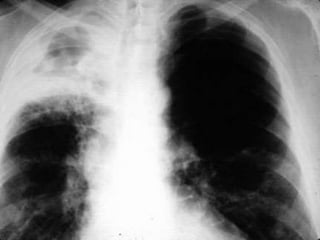

Tuberculosis and meningitis are infectious diseases that can be deadly if not properly treated. Meningitis in particular can kill and its transmission must be controlled through proper distribution methods. The presentation provided an orientation on these diseases and thanked attendees for listening.